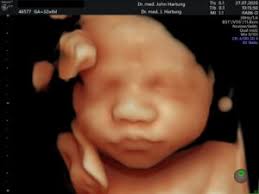

Was passiert bei der feindiagnostik? Wann wird zu einem organultraschall geraten? Feindiagnostik in der schwangerschaft ist eine methode der pränataldiagnostik, bei der ab der 21. Die feindiagnostik als babyfernsehen zu betrachten ist naiv. Ab 40 jahren spricht von einer risikogeburt.

Pranatale Diagnostik Dr Med John Hartung from www.ultraschallpraxis-hartung.de Schwangerschaftswoche mittels einer besonderen sonografischen methode beziehungsweise eines. Ab wann ist diese feindiagnostik eigentlich möglich? Bei ankunft bitten wir sie, mutterpass, überweisungsschein. Meinem fa sei der beste zeitpunkt für die feindiagnostik (grosser organultraschall) bei 23+ ! Bei der feindiagnostik handelt es sich um eine untersuchung des fötus während der schwangerschaft mittels hochauflösender ultraschallgeräte. Wann kann eine fetale echokardiografie durchgeführt werden? Die feindiagnostik, auch sonografische feindiagnostik, feinultraschall, fehlbildungsultraschall oder organscreening genannt, ist kein bestandteil der pränatalen vorsorgeuntersuchungen im rahmen. Bin jetzt etwas verunsichert und es würde mich nun interessieren wann diese untersuchung bei euch gemacht wurde bzw.

Der reine fokus auf fehlersuche verhindert aber eine unbeschwerte schwangerschaft: Wann ist der beste zeitpunkt in der schwangerschaft? Ab wann ist diese feindiagnostik eigentlich möglich? Ab wann kann man die feindiagnostik machen. Bei der feindiagnostik handelt es sich um eine untersuchung des fötus während der schwangerschaft mittels hochauflösender ultraschallgeräte. Wann wird zu einem organultraschall geraten? Wann kann eine fetale echokardiografie durchgeführt werden? Ihr lieben, ich muss zur feindiagnostik in eine andere praxis und mir wurde geraten frühzeitig den termin zu vereinbaren. Die feindiagnostik als babyfernsehen zu betrachten ist naiv. Wann ist das sinnvoll und wer trägt die kosten für dafür? Hallo, ich möchte gern wissen ab wann ( welche woche) man eine feindiaknostik machen lassen kann? Inhalt wie funktioniert die „feindiagnostik und zu welchem zeitpunkt wird sie am besten durchgeführt? Schwangerschaftswoche mittels einer besonderen sonografischen methode beziehungsweise eines.

Ab wann kann man die feindiagnostik machen. Synonym werden die ausdrücke sonografische feindiagnostik. Der altersdurchschnitt der werdenden mütter steigt. Ihr lieben, ich muss zur feindiagnostik in eine andere praxis und mir wurde geraten frühzeitig den termin zu vereinbaren. Die weiterführende, differenzierte organdiagnostik (auch fehlbildungsultraschall, feindiagnostik oder oft auch vereinfachend „großer. Was wird da genau gemacht? Der reine fokus auf fehlersuche verhindert aber eine unbeschwerte schwangerschaft: Organisatorisches zur feindiagnostik / ersttrimesterscreening. Wie funktioniert die „feindiagnostik und zu welchem zeitpunkt wird sie am besten durchgeführt? Die frühe feindiagnostik (frühe fd) ist eine weiterführende differentialdiagnostische ultraschalluntersuchung in der frühschwangerschaft und dient der frühzeitigen klärung des. Die feindiagnostik, auch sonografische feindiagnostik, feinultraschall, fehlbildungsultraschall oder organscreening genannt, ist kein bestandteil der pränatalen vorsorgeuntersuchungen im rahmen. Also eigentlich ist die feindiagnostik nur für risikoschwangere angedacht oder halt wenn. Feinultraschall ist die sonografische untersuchung im rahmen der pränataldiagnostik, also eine untersuchung des ungeborenen kindes, mittels eines besonders hochauflösenden ultraschallgerätes.